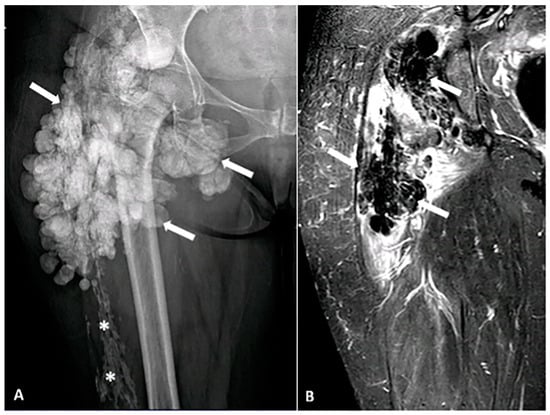

5.2.2. Primary Tumoral Calcinosis

- Fathi, I.; Sakr, M. Review of tumoral calcinosis: A rare clinico-pathological entity. World J. Clin. Cases WJCC 2014, 2, 409. [Google Scholar]

- Zanatta, E.; Desportes, M.; Do, H.H.; Avouac, J.; Doria, A.; Feydy, A.; Allanore, Y. Pseudotumoral calcinosis in systemic sclerosis: Data from systematic literature review and case series from two referral centres. Semin. Arthritis Rheum. 2020, 50, 1339–1347. [Google Scholar]

- Daumas, A.; Rossi, P.; Ariey-Bonnet, D.; Bernard, F.; Dussol, B.; Berbis, P.; Granel, B. Generalized calcinosis in systemic sclerosis. QJM Int. J. Med. 2014, 107, 219–221. [Google Scholar]

- Fabbri, L.; Fusaroli, M.; Catizone, L.; Zucchelli, P. Periaticular metastatic calcifications in uremic patients. Minerva Medica 1975, 66, 209–219. [Google Scholar]